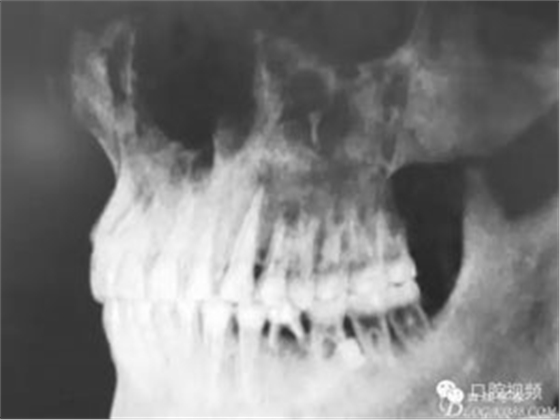

圖1.術(shù)前的全景片影像檢查,35移位至36、37之間。

圖2.術(shù)前的CBCT,35移位至36、37之間的舌側(cè)。

患者、盧xx、男、19歲。主訴:左側(cè)下頜乳磨牙未脫落,要求檢查。??茩z查:左側(cè)下頜第二乳磨牙有充填物。無松動,全景片檢查。35移位至36、37之間。頰舌側(cè)均不能觸及隆起。CBCT檢查:35位于36、37的舌側(cè)。表面骨質(zhì)約2mm左右。35完全骨埋伏,36的遠中牙根疑是吸收。建議35暫觀察。置留不取。患者要求拔除擔(dān)心壓迫36牙根或者發(fā)生囊性變。術(shù)前簽手術(shù)同意書。